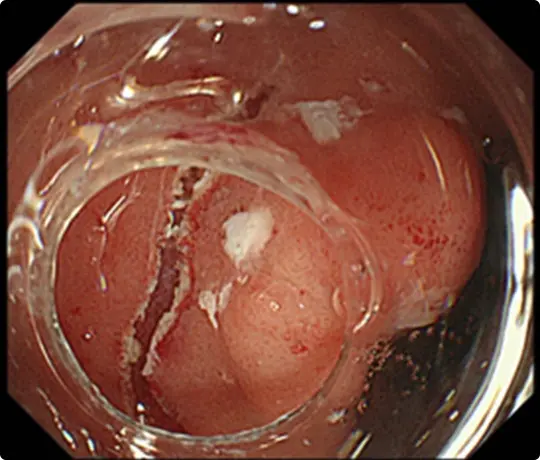

スネアでポリープの根元を縛り、電流を流して切除します(出血予防のためポリープの根元にクリップをうっています)。

切除した検体です。病理検査で早期大腸がんと診断されました。がんは完全に切除されており、治癒と判定されました。